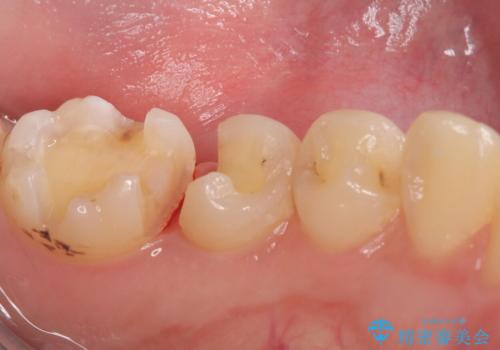

- 主訴:銀の詰め物が取れた、奥の銀の詰め物も一緒に白くしたい

保険適用のメタルインレーの脱離で来院されました。審美性、適合性、清掃性の観点から2本ともセラミックインレーでのやり替えとなりました。

保険適用のメタルインレーはセラミックやゴールドに比べるとプラークなどの汚れが付きやすく、また今回はそこまで大きなう蝕は広がっていませんでしたが、適合性に限界があるためインレーと歯質との境目で二次う蝕が発生する可能性が高くなります。